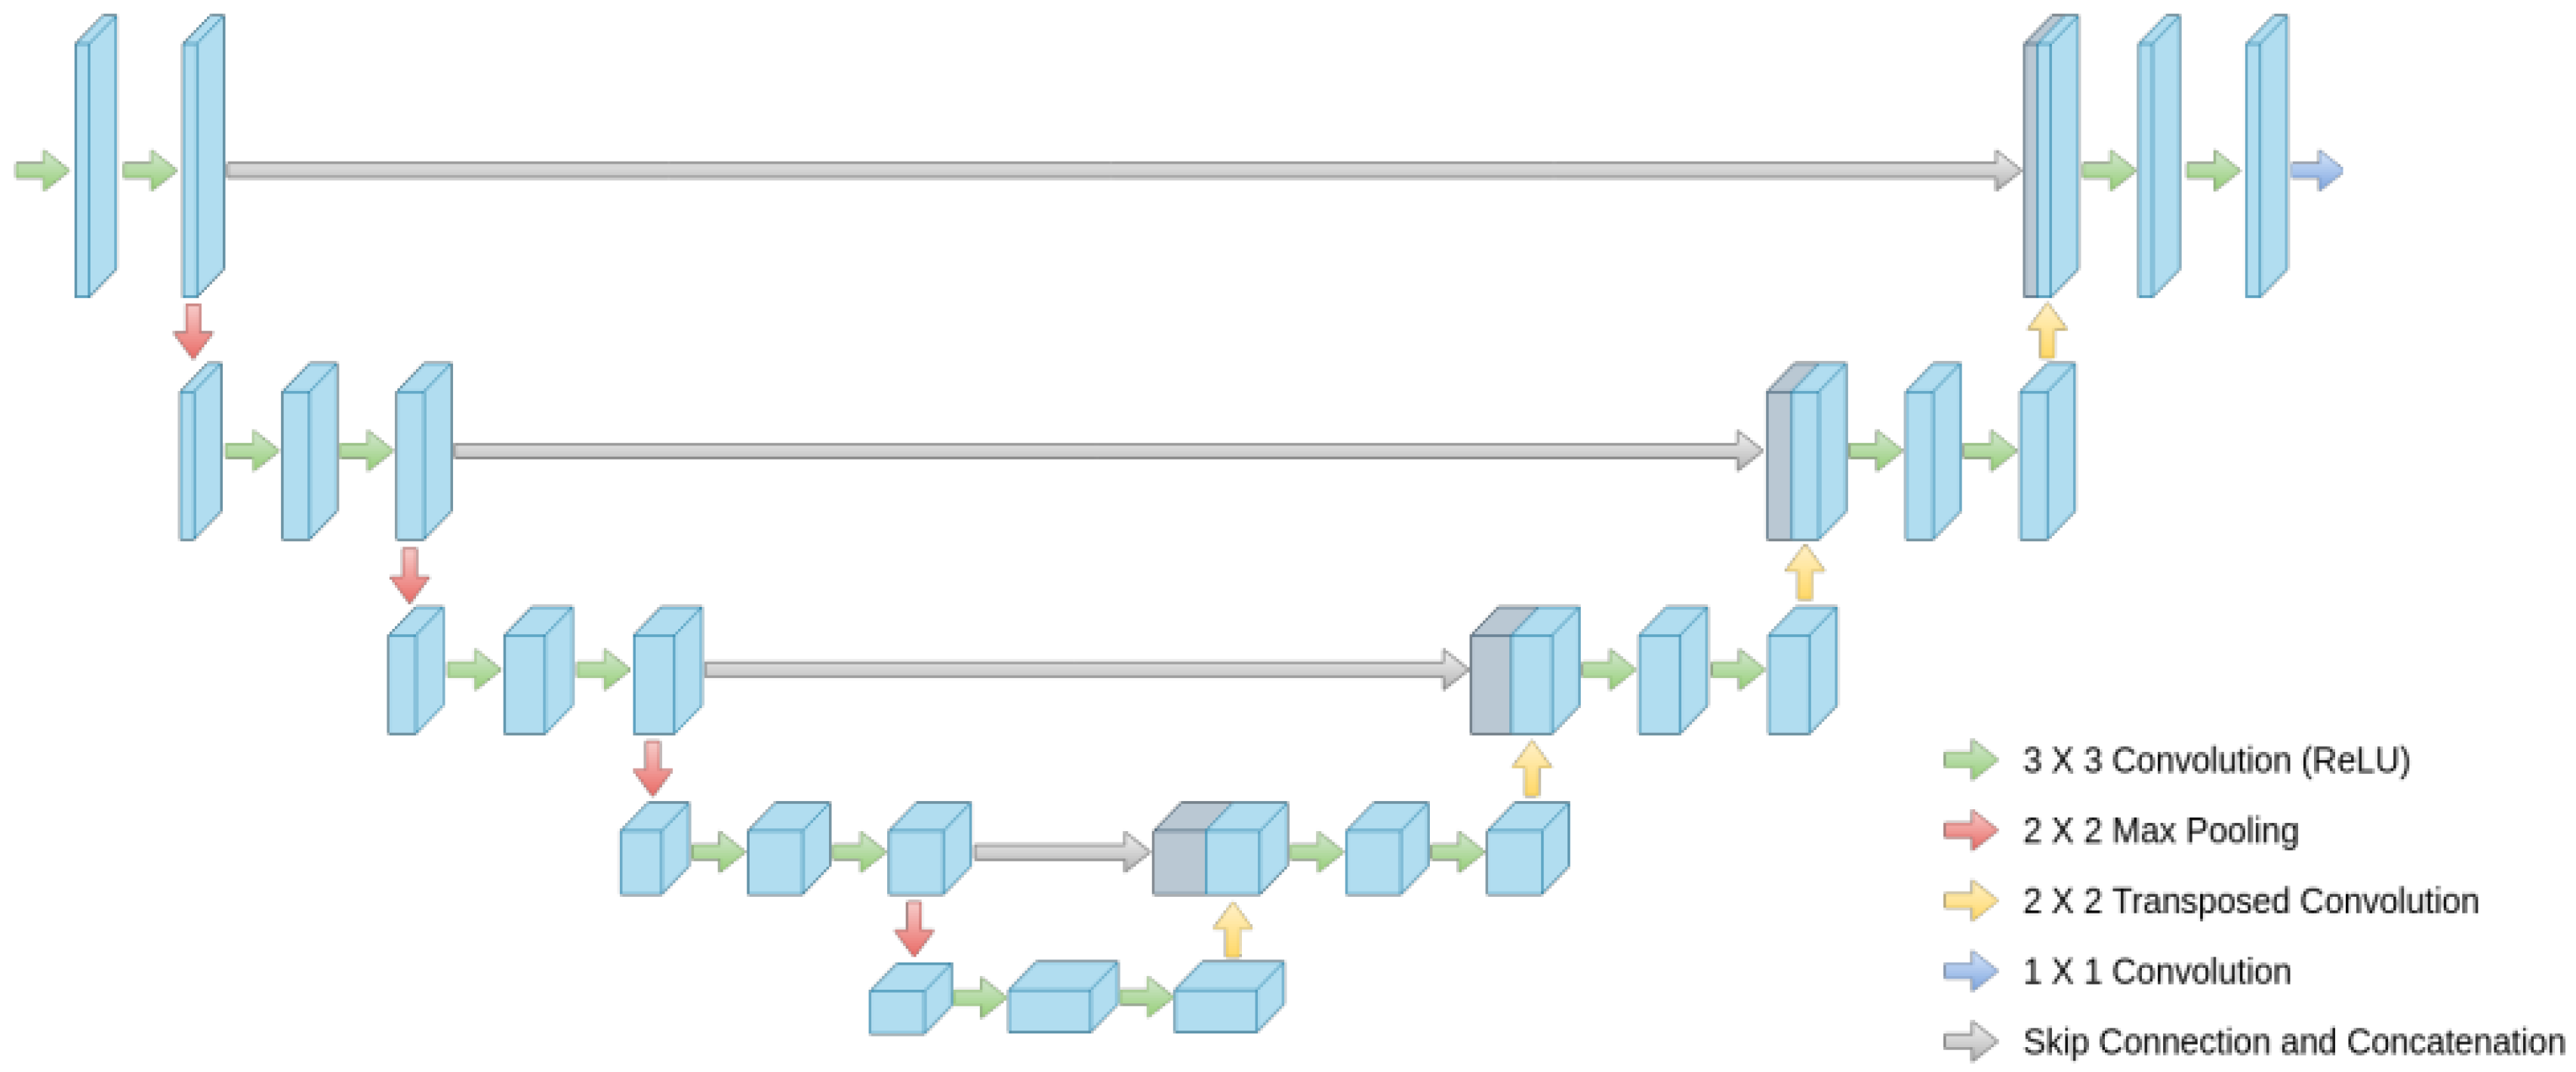

2.2. Methods

2.2.1. Encoder

2.2.2. Decoder